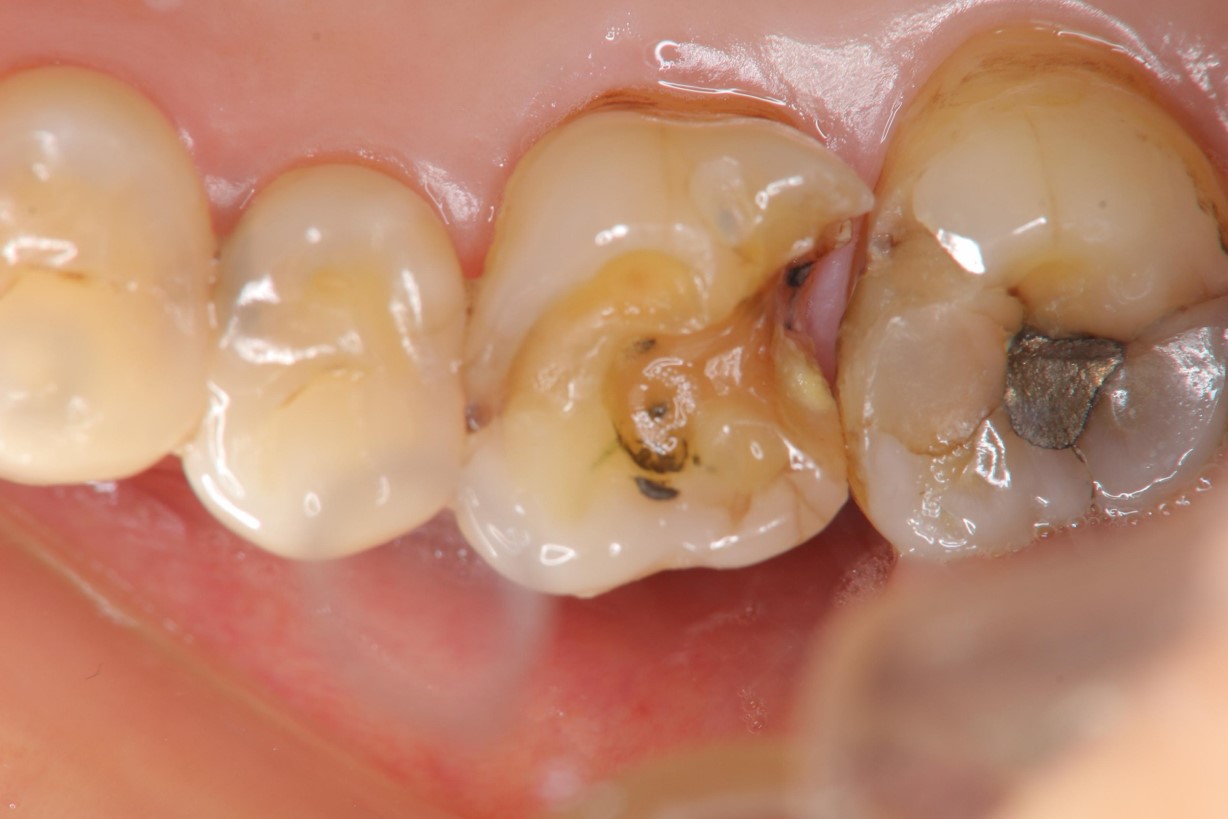

瓷塊製備